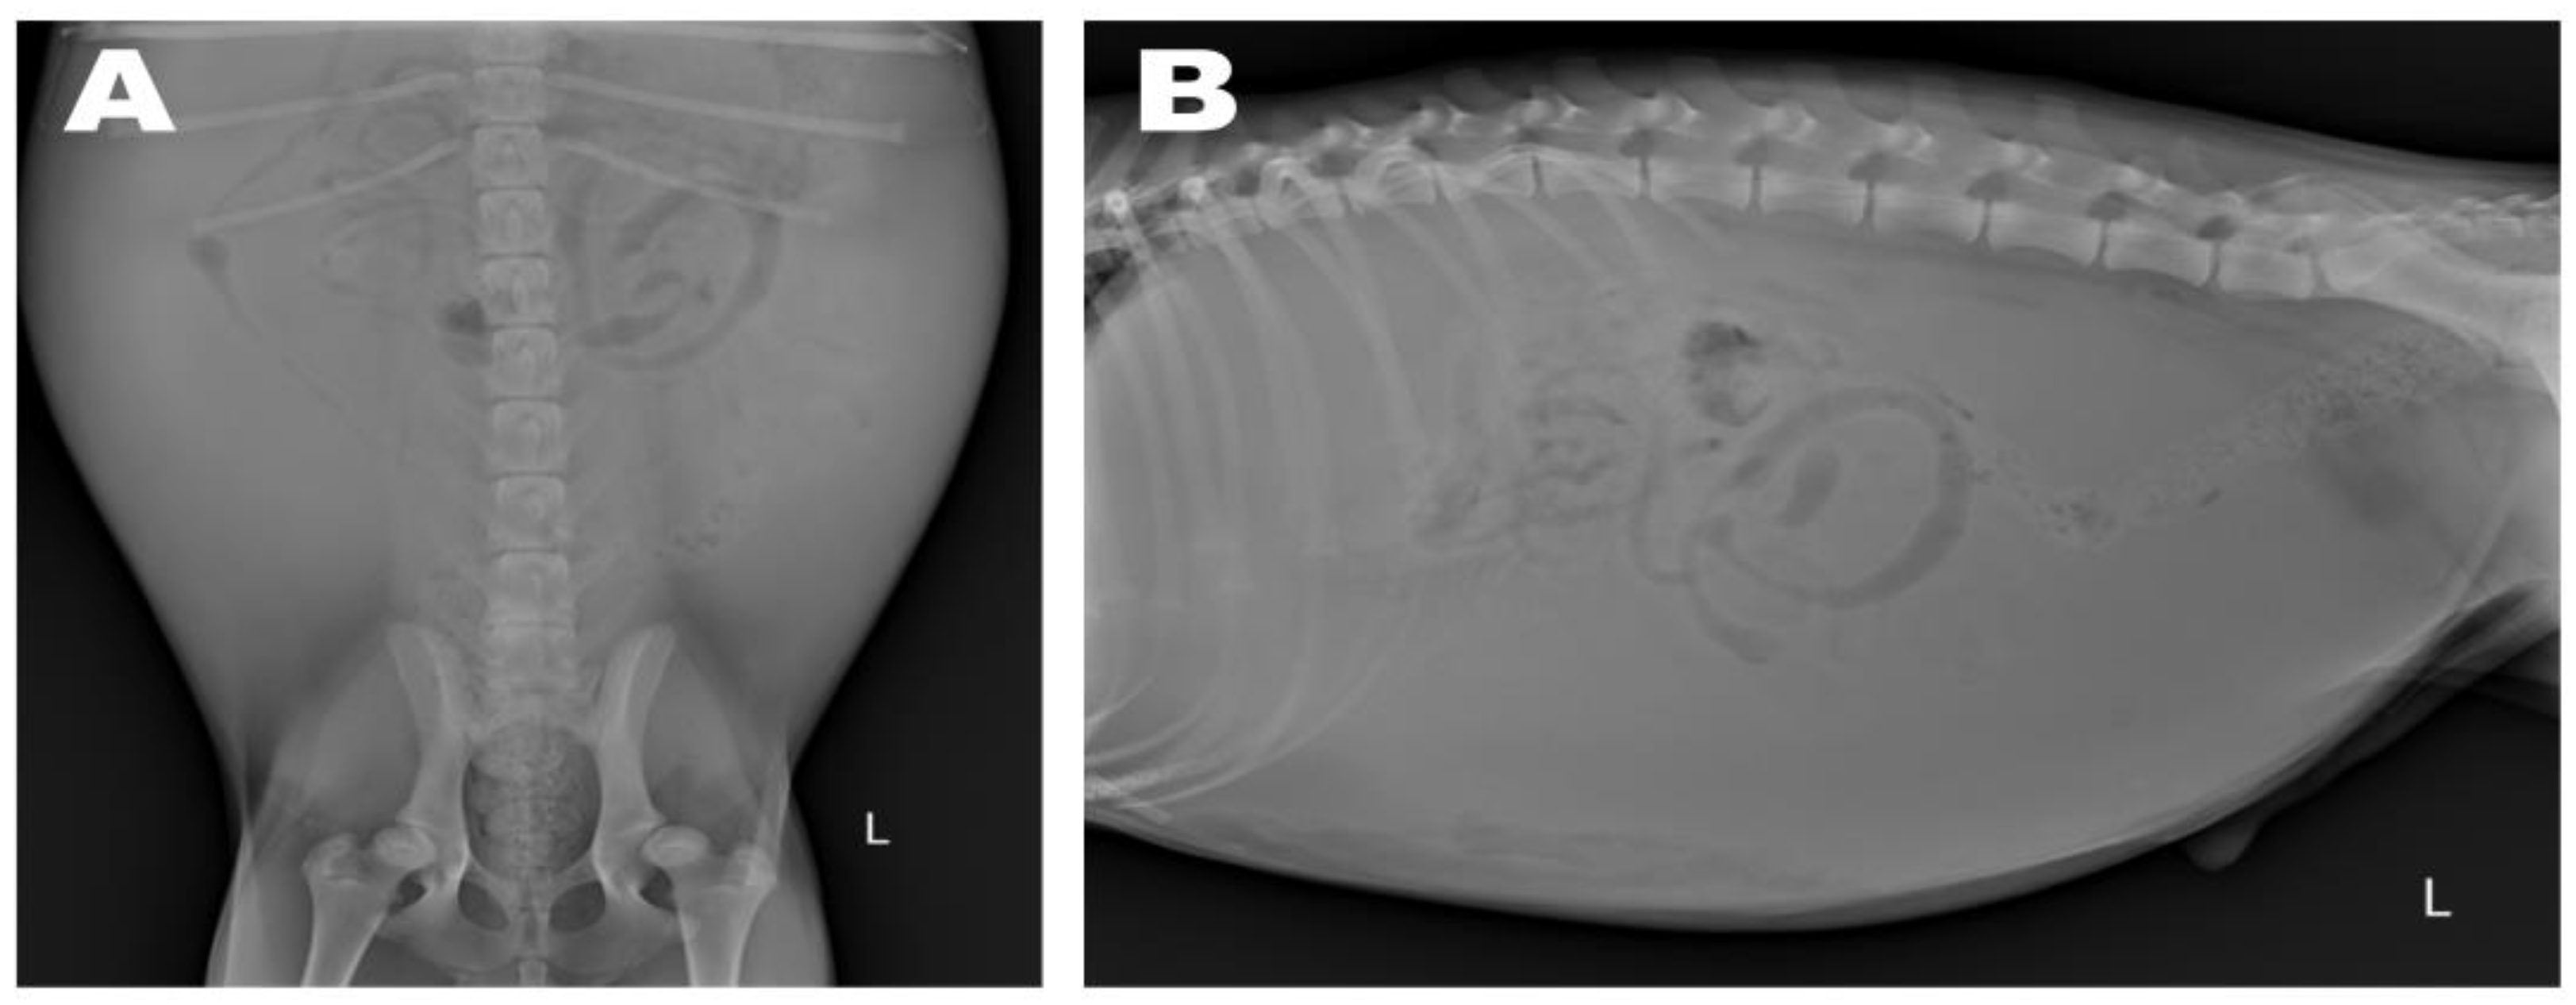

Abdominal radiographs showed severe abdominal distention and a loss of serosal detail (Figure 1); no significant findings were observed apart from these. Transthoracic echocardiography showed an echo-dense, band-like structure within the right atrial chamber, extending from the atrioventricular junction to the free atrial wall (Figure 2A). The right atrium was divided into cranial and caudal chambers. Color Doppler imaging revealed continuous venous blood inflow from the caudal chamber to the cranial chamber through a perforation in the remnant membrane, confirming an abnormal venous blood inflow in the right atrium. An agitated saline study was performed using 3 mL of normal saline to further characterize the flow in the right atrium. Microbubbles were made with saline solution, two syringes, and a three-way stopcock. These were injected in the left cephalic vein and the contrast was noted only in the right atrial cranial chamber and the right ventricle immediately afterward (Figure 2B). When the microbubbles were injected in the left lateral saphenous vein, these reached immediately the right atrial caudal chamber; and some moved into the cranial chamber through a perforated membrane (Figure 2C). This confirmed the presence of a cranial true chamber (CrTC) and cranial vena cava (CrVC) as well as a caudal accessory chamber (CdAC) and caudal vena cava (CdVC). A thoracic computed tomography scan was performed using 30 mL of iohexol contrast agent (Omnipaque, GE Healthcare China). Strong contrast enhancement was observed in the cranial chamber that communicated with the CrVC (Figure 3) during the dextrophase (25 s after contrast injection); in contrast, weak contrast enhancement was observed in the caudal chamber connected to the CdVC. A venous blood inflow obstruction was observed in the right atrium connected to the CdVC, suspected of causing severe ascites. Based on these imaging findings, the patient was diagnosed with CTD, and surgical correction was advised. Both interventional procedures and open-heart surgery can be options for treating CTD. However, considering the potential risk of re-stenosis following interventional treatment, a curative resection involving surgical membranectomy via VIO was planned.

Figure 1. Preoperative abdominal radiography: ventrodorsal (A) and lateral (B) views. Severe abdominal distention and decreased serosal detail were observed due to ascites.